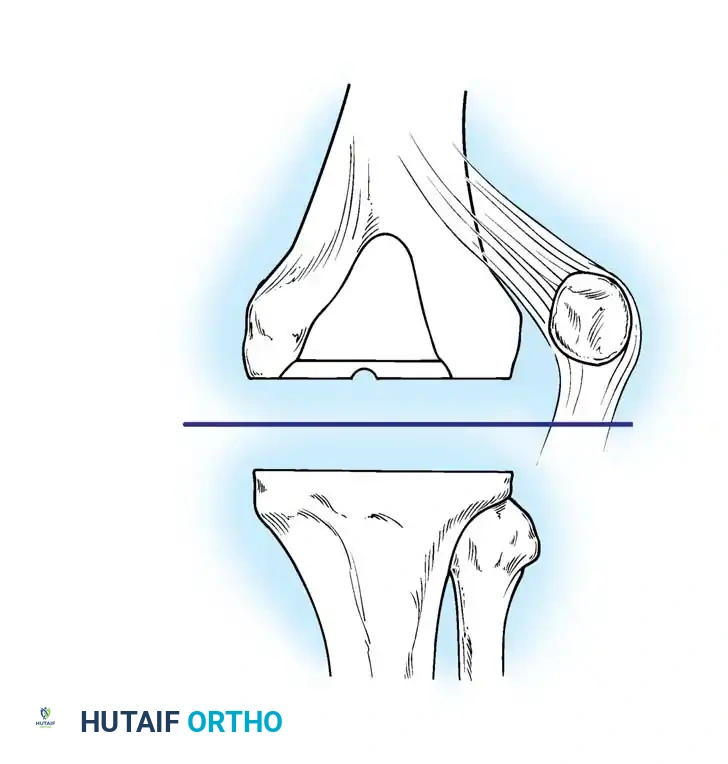

Instability

Instability is an increasingly prevalent indication for revision TKA, accounting for approximately 20% of all revisions in longitudinal studies by Fehring and Valadie.

Fig. 6-74 Instability may be an indication for revision knee arthroplasty.

The primary etiologies of instability include:

1. Ligamentous Imbalance: Failure to balance the flexion and extension gaps during the index procedure.

2. Late Ligamentous Incompetence: Attenuation of the medial collateral ligament (MCL) or posterior cruciate ligament (PCL) over time.

3. Extensor Mechanism Deficiency: Patellar tendon rupture or severe patellofemoral maltracking.

4. Surgical Error: Improper bone cuts altering the joint line or component rotation.

Routine knee aspiration in unstable knees often reveals a preponderance of red blood cells (averaging 64,000/mm³), indicative of chronic synovial impingement and recurrent hemarthrosis.